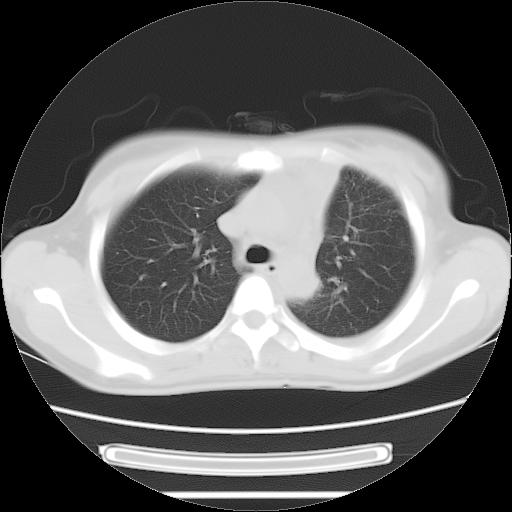

女,29岁,胸部不适,在外院胸片提示胸腔积液,到我院ct检查。

肺窗:

1、左侧包裹性积液伴叶间积液 2、右肺多发结节考虑增殖结节

考虑:1.两肺tb;2.左侧胸膜炎、胸腔积液。

考虑两肺结核,左侧包裹性积液,叶间积液。

右肺多发结节。左胸腔多发包裹性积液。